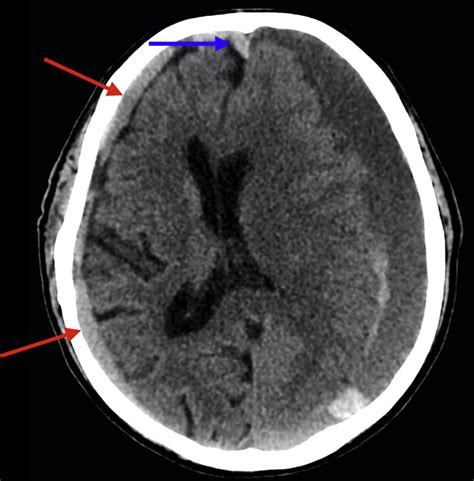

Interpreting Subdural Hemorrhage CT Images

Interpreting Subdural Hemorrhage CT Images requires a trained eye. Radiologists look for specific signs that indicate the presence of a subdural hemorrhage. These signs include:

• Hyperdense crescent-shaped collections of blood between the skull and the brain.

• Midline shift, where the brain is pushed to one side due to the pressure from the hemorrhage.

• Effacement of the sulci and ventricles, indicating compression of the brain tissue.

These findings help in diagnosing the type and severity of the subdural hemorrhage.

• Acute Subdural Hemorrhage: Occurs within 72 hours of the injury and appears as a hyperdense collection on CT images.

Case Study 1: A 65-year-old patient presented with a sudden onset of severe headache and vomiting. A CT scan revealed a hyperdense crescent-shaped collection consistent with an acute subdural hemorrhage. The patient underwent emergency surgery to evacuate the blood, and follow-up CT scans showed resolution of the hemorrhage.